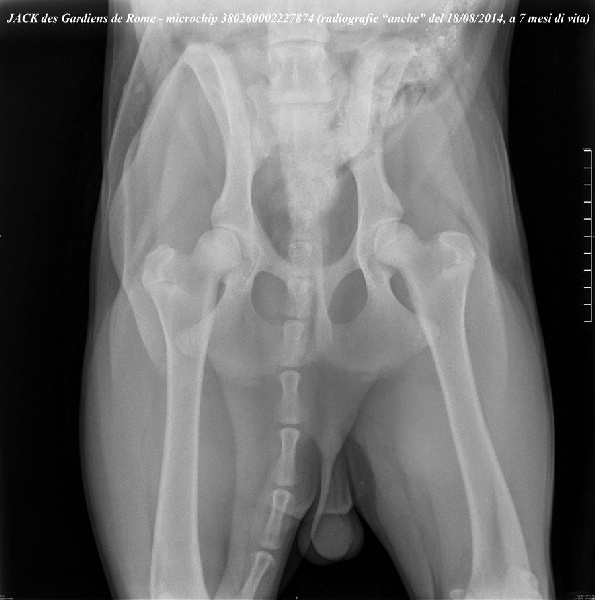

Jack Des Gardiens De Rome

| Puce | 380260002227874 |